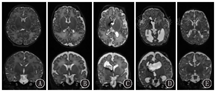

1 头颅MRI评估的发展历史早在1983年,Johnson等[3]首次报道了头颅MRI应用于新生儿脑发育及损伤的评估,展示了从胎龄36周至出生后20月龄不同时期髓鞘化的水平(图1);同时提供了早产儿脑室旁出血和后期白质软化、侧脑室扩张等病变(图2)。

髓鞘化进程 A:纠正胎龄36周;B:纠正胎龄42周;C:纠正胎龄52周;D:10月龄时;E:20月龄时

Myelination process A:36 weeks postmenstrual age;B:42 weeks postmenstrual age;C:52 weeks postmenstrual age;D:full term infant at 10 months;E:full term infant at 20 months